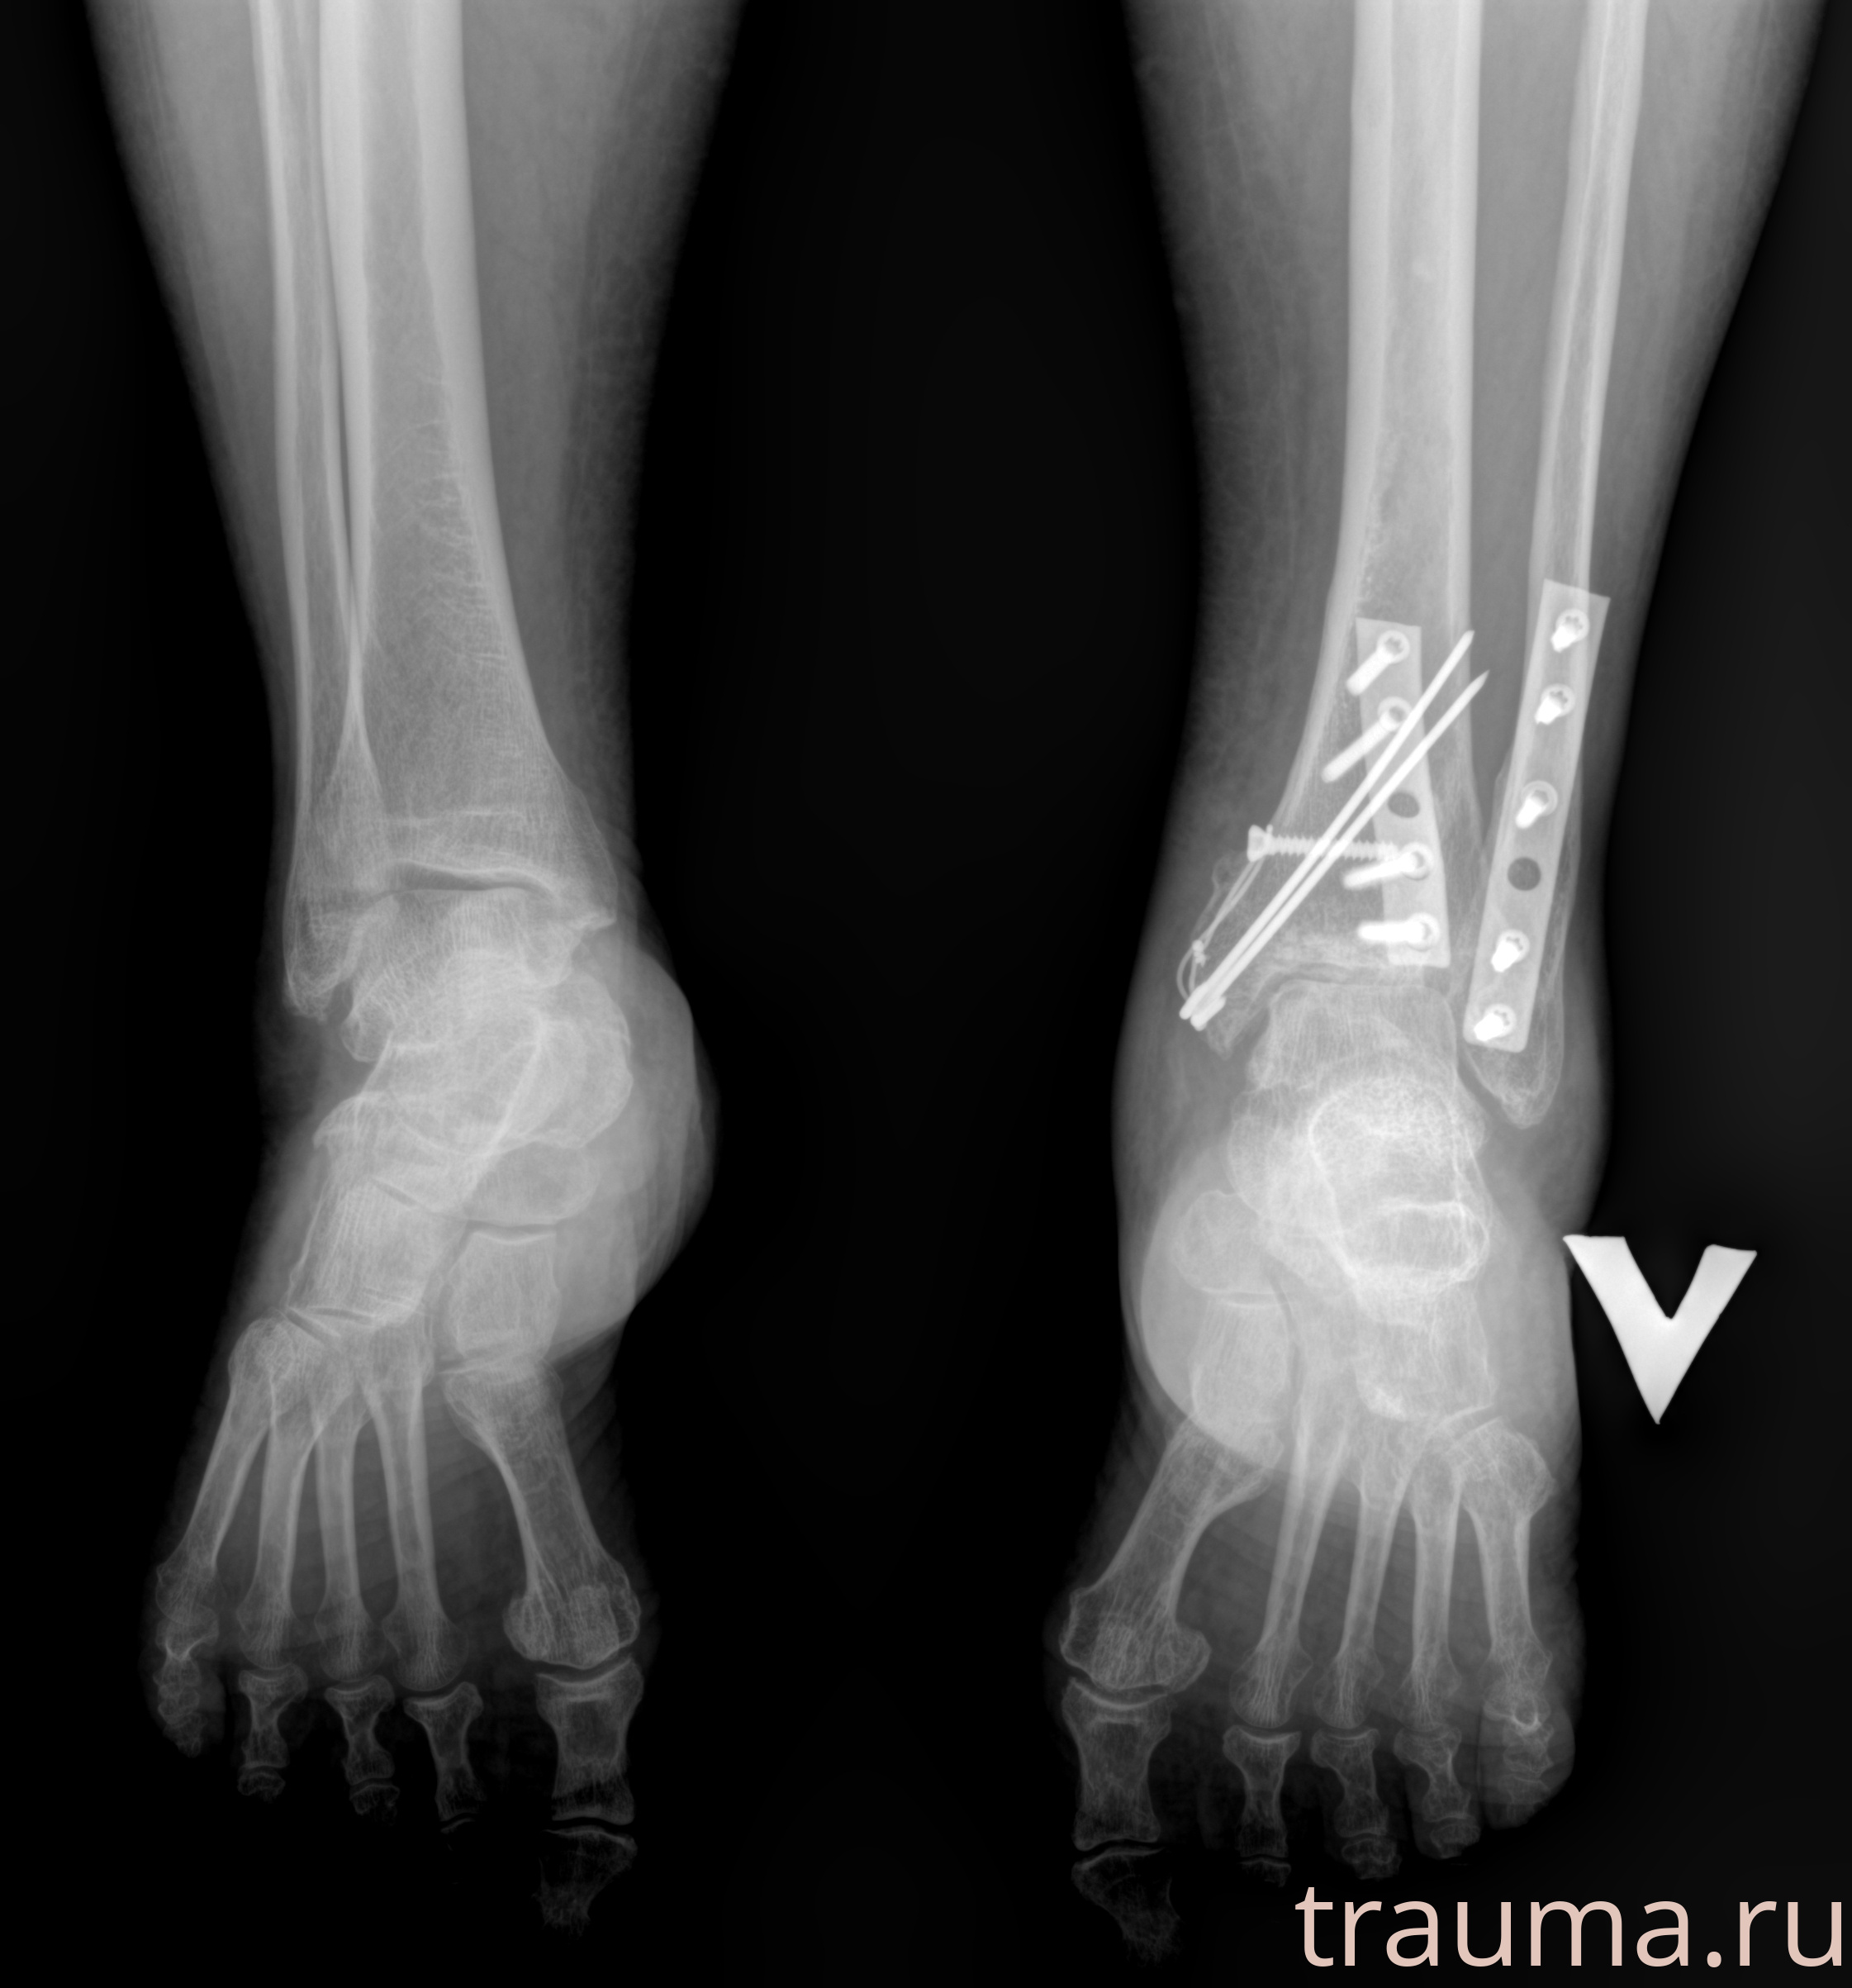

Рентгенограммы

Рентген на дому: по вашему адресу приезжает врач-рентгенолог, травматолог-ортопед с мобильным рентгеновским аппаратом, проводит диагностику травмы или заболевания, делает необходимые рентгенограммы, дает рекомендации по дальнейшему лечению. Получить качественные снимки в домашних условиях возможно благодаря уникальной методике, разработанной МосРентген Центром для института  Склифосовского